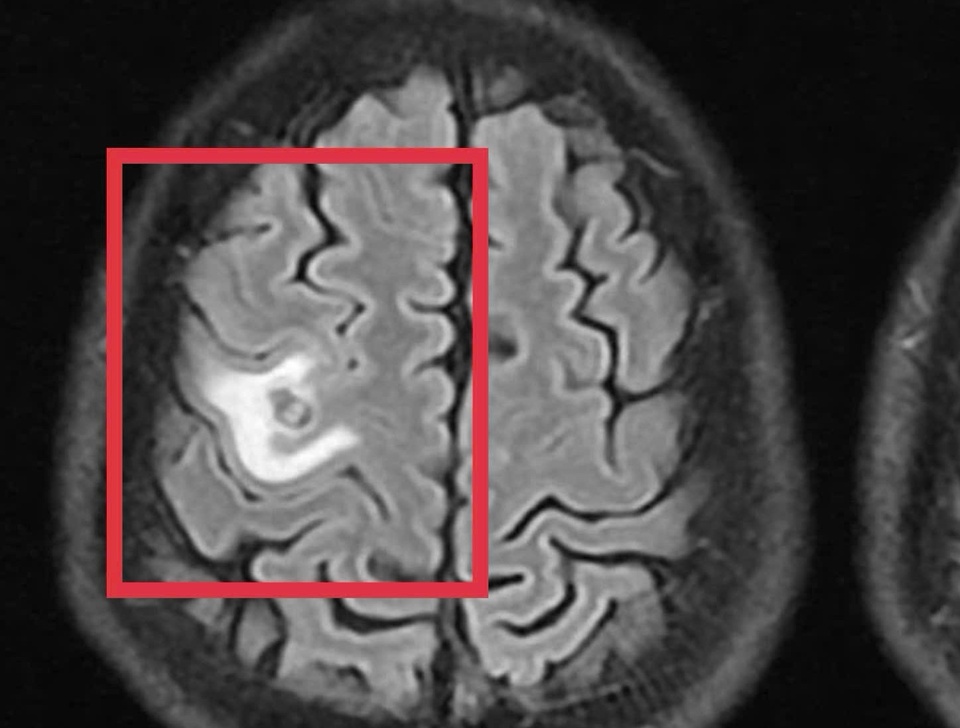

Bệnh nhân được chụp cộng hưởng từ (MRI) sọ não, phát hiện tổn thương dạng nang nhỏ tại thùy trán trái, kích thước khoảng 11 x 7 mm, xung quanh có phù não nhẹ. Ảnh: BVCC.

Bệnh nhân được chụp cộng hưởng từ (MRI) sọ não, phát hiện khiến bác sĩ bất ngờ khi thấy nhiều tổn thương dạng nang nhỏ tại thùy trán trái, kích thước khoảng 11 x 7 mm, xung quanh có phù não nhẹ. Hình ảnh này hướng nhiều đến tổn thương do ký sinh trùng hơn là u não nguyên phát.